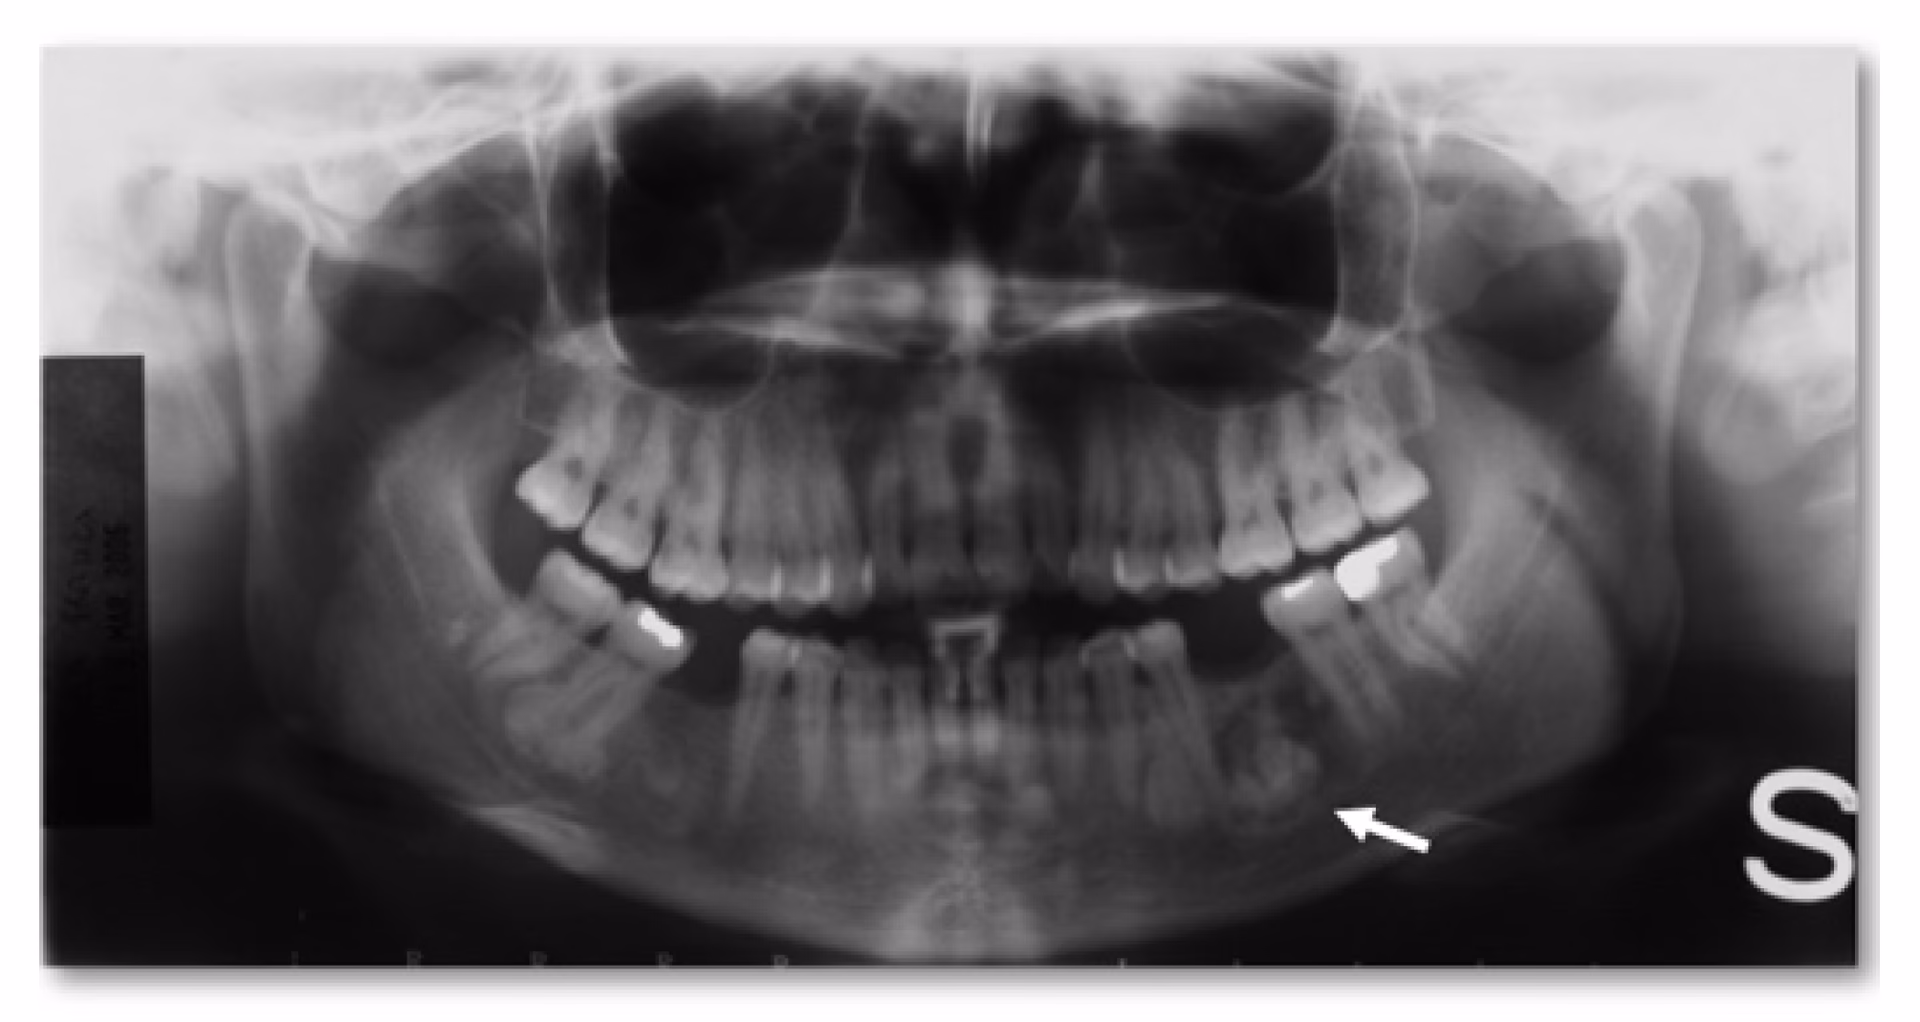

Estos tumores óseos pueden formarse en cualquier lugar del cráneo y su tamaño puede variar. Son comunes en la mandíbula y los senos nasales, aunque a veces también pueden desarrollarse en el área del cuello. Los osteomas pueden afectar a cualquier persona.